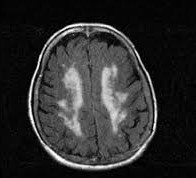

• La leucoaraiose

La leucoaraiose (ou leucoaraïose) témoigne d'une atteinte de la substance blanche cérébrale d'origine vasculaire (atteinte des petits vaisseaux). Elle s'observe chez les patients âgés.